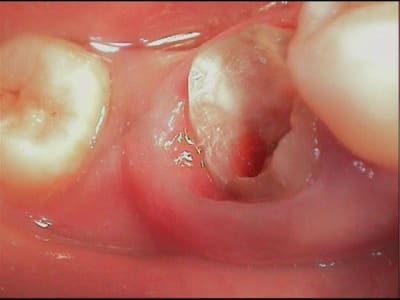

en déposant délicatement le compo, je trouve donc ça (photos) et c'était plutôt bien fait, j'imagine que le prat a craint d'avoir trop de contraintes canalaires avec un ancrage différent, moralité les contraintes ce sont accumulées au tiers cervical et c'est là que ça a cassé.